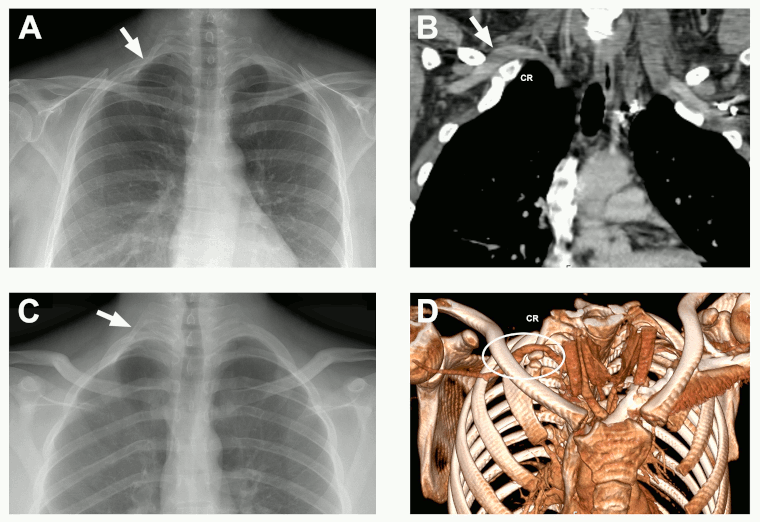

Bony abnormalities are present in 5% to 10% of patients with neurogenic TOS and in almost all patients with arterial TOS, occurring as partial or complete cervical ribs (articulated with the first rib), hypoplastic first ribs, bridging fusion between the first and second ribs, first rib fractures, or clavicular deformities.[106][107] An initial chest x-ray and/or cervical spine x-ray can reveal these abnormalities and is the initial diagnostic test for all patients with TOS.[1][108]

[Figure caption and citation for the preceding image starts]: Cervical ribs. Chest radiographs demonstrating a patient with a partial cervical rib on the right side (A) and a patient with a complete cervical rib on the left side (B)From the collection of Robert W. Thompson, MD; used with permission [Citation ends].

If arterial TOS is suspected, the presence of a cervical rib or other bony abnormality can be easily assessed by CXR. Vascular Doppler ultrasound studies are useful to analyse dynamic flow in the axillary and subclavian arteries and detect any thrombosis, stenosis, or aneurysmal changes.[1][108] CT angiography is recommended to demonstrate arterial compression.[1][108] MR angiography may identify the cause and severity of arterial TOS, and guide surgical or endovascular management.[108] Conventional arteriography may also be performed but has been largely replaced by alternative imaging for diagnosis and is mostly used during surgery for arterial TOS.

[Figure caption and citation for the preceding image starts]: Subclavian artery aneurysms. (A and B): Plain chest radiograph showing complete cervical rib on the right side (arrow) and an image from CT angiogram showing a subclavian artery aneurysm arising immediately past the point of arterial compression by the cervical rib (arrow). (C and D): Plain chest radiograph showing complete cervical rib on the right side (arrow) and a 3-D reconstruction from a CT angiogram demonstrating a subclavian artery aneurysm immediately past the point of arterial compression by the cervical rib (oval highlight). CR: cervical ribFrom the collection of Dr. Robert W. Thompson; used with permission [Citation ends].